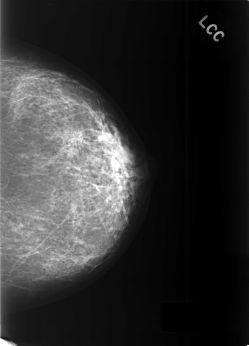

C_0377_1.LEFT_CC

LEFT_CC LINES 5528 PIXELS_PER_LINE 3984 BITS_PER_PIXEL 12 RESOLUTION 50 NON_OVERLAY